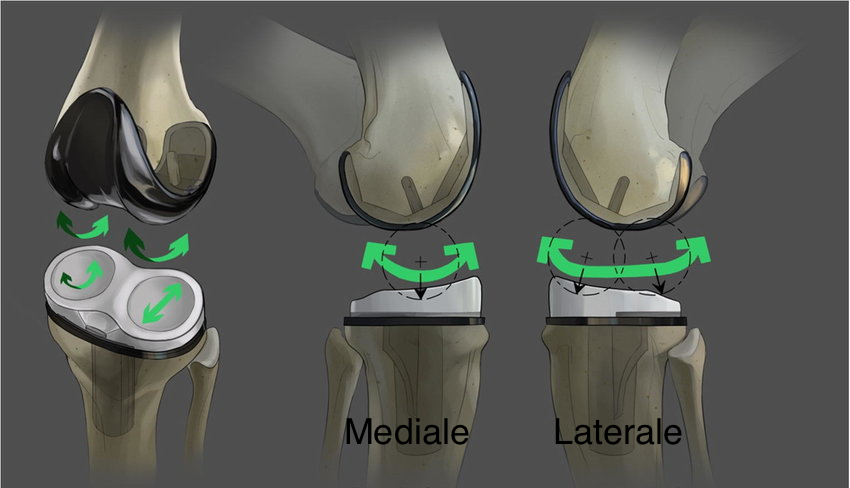

UKA mediale vs UKA laterale: differenze pratiche

UKA mediale (AMOA come scenario tipico)

Pattern classico: usura antero-mediale, compartimento laterale preservato, ACL funzionale, deformità in varo correggibile.

UKA laterale

Meno frequente e più “selettiva” per anatomia/biomeccanica, ma con indicazioni ben descritte:

OA laterale moderata-severa con compartimento mediale a cartilagine a tutto spessore, legamenti integri, deformità in valgo correggibile e contrattura limitata (spesso <10–15°). Controindicazioni ricorrenti: artrite infiammatoria e coinvolgimento patello-femorale severo.

La scelta del design (mobile-bearing vs fixed-bearing) influenza pattern di complicanze e fallimenti (es. dislocazione del bearing vs usura/instabilità, a seconda del sistema e del compartimento), e va coerentata con stabilità, allineamento e “fenotipo” del ginocchio.